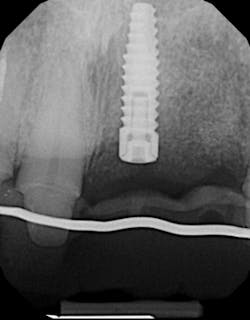

There are many different methods clinicians use to measure the maturity of the bone around the dental implant. Bone-to-implant contact is one measure of determining when implants are ready to load. Intraoral/panoramic radiographs, cone beam computed tomography (CBCT), microcomputed tomography (MCT), reverse torque testing, and resonance frequency analysis (RFA) are all methods that have been documented in the literature. The ability of standard imaging techniques, such as periapical and panoramic radiography, to measure bone-to-implant contact and integration levels have been questioned since standard imaging lacks the sensitivity needed for accurate assessment. (4) These two-dimensional radiographs may show bone surrounding an implant even when bone-to-implant contact levels are low (figure 1).